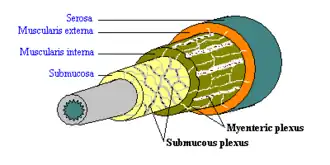

The myenteric plexus shown in the muscular layer of the gastrointestinal tract | |

A part of the enteric nervous system, the myenteric plexus exists between the longitudinal and circular layers of muscularis externa in the gastrointestinal tract. It is found in the muscles of the esophagus, stomach, and intestine.